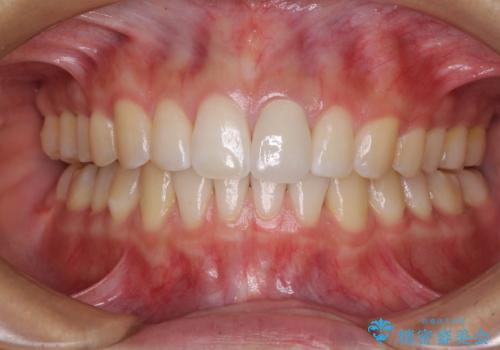

- 変色した前歯と突出した口元を気にして来院された患者様です。

口元の突出感はインビザラインにより歯列を整え、その後に、前歯をオーダーメイドタイプのオールセラミッククラウンにて補綴治療することとしました。

長時間のマウスピース装着と、患者様自身でのゴムかけに協力いただき、口元の突出感をしっかりと改善することができました。

前歯のオールセラミッククラウンもまるで本物の歯のように仕上がり、患者様には大変満足していただきました。